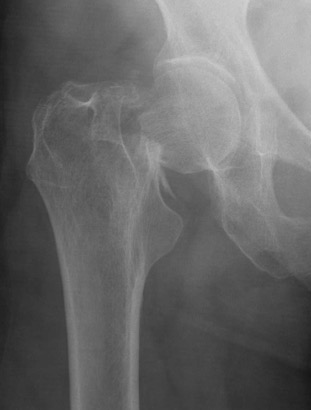

Type I: Incomplete, valgus impacted fracture

Type II: Complete fracture, undisplaced

Type III: Complete fracture, partial displaced, trabeculae don't line up with acetabulum

Type IV: Complete fracture, completely displaced, trabeculae line up with acetabulum

Garden's Classification

| Garden | Description | Displacement |

| I |

Incomplete Valgus impacted Lateral cortex fractured Medial cortex intact |

Undisplaced |

| II | Complete | Undisplaced |

| III |

Complete fracture Partial displacement Trabeculae don't line up with acetabulum |

Displaced |

| IV |

Complete fracture Complete displacement Trabeculae line up with acetabulum |